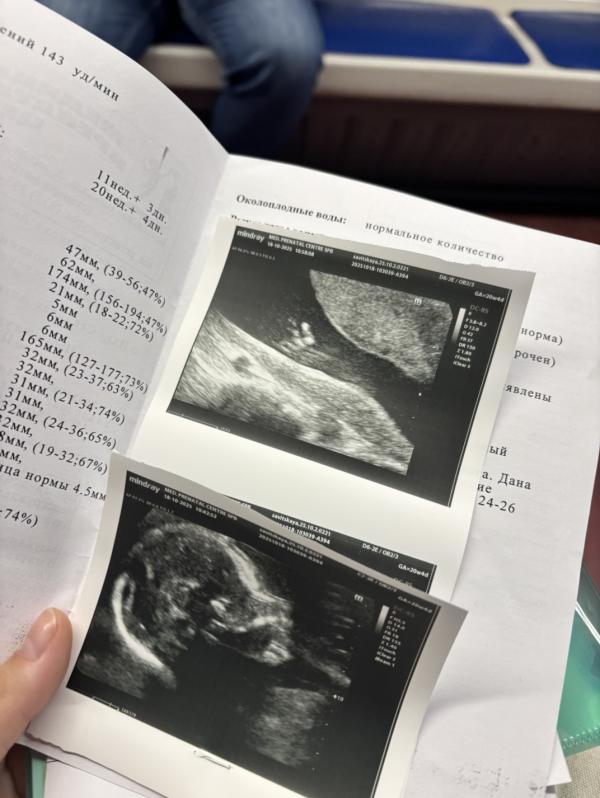

Сходила позавчера с мужем на 2 скрининг,сказали что с развитием все хорошо-но врач не смогла найти 3 фаланг мизинчика на кисти,и показала что на ножках большой пальцы оттопыренны (4 фото видео с узи-муж говорит все видно,а на ногах у тебя также оттопырен палец ),при 1 скрининге сдала кровь,низкие риски на 21 хромосому.

Порекомендовали сдать нипт,я уже накрутила себя .(1 скрининг делали платно-2 скрининг в этой же поликлинике сделали бесплатно через гинеколога)